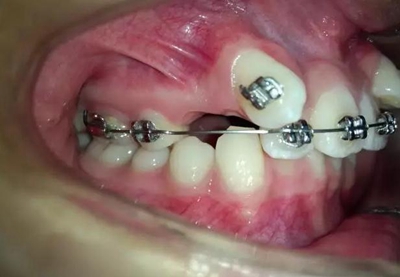

14歲,牙齒嚴(yán)重?fù)頂D,上頜兩個(gè)尖牙在側(cè)切牙唇側(cè)

采用細(xì)絲排齊,8字結(jié)扎控制尖牙,此時(shí)如果直接拉尖牙,勢(shì)必導(dǎo)致上頜磨牙近中移動(dòng),更何況磨牙本來就是遠(yuǎn)中關(guān)系,需要強(qiáng)支抗。

幾個(gè)月后,換上不銹鋼方絲,側(cè)切牙遠(yuǎn)中彎制了一個(gè)內(nèi)展彎,避免了尖牙遠(yuǎn)中移動(dòng)時(shí)與弓絲形成頜干擾。

考慮了一下沒有采用其他輔助裝置和種植支抗,還是采用輔弓增加支抗,經(jīng)濟(jì)適用,也便與操作,0.8不銹鋼絲彎制,進(jìn)行熱處理,增加其彈力。

結(jié)扎固定后開始牽引尖牙向遠(yuǎn)中,

兩個(gè)月后效果還是比較明顯的。